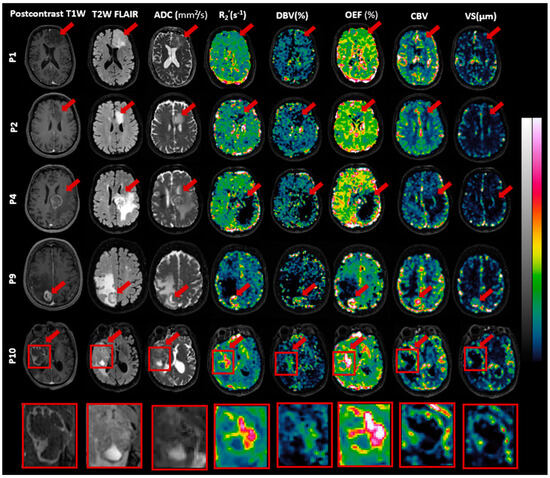

3.3. Features of MRI Parametric Maps

| VOI | R2′ (s–1) | DBV (%) | OEF (%) | CBV | Vessel Size (µm) |

|---|---|---|---|---|---|

| Contra-GM (n = 10) | 5.13 (1.74) | 4.30 (1.60) | 43.89 (16.88) | 1.66 (0.33) | 16.24 (3.14) |

| Edema (n = 4) | 3.21 (0.58) | 7.43 (2.73) | 21.06 (7.08) | 0.71 (0.13) | 16.78 (5.72) |

| Nonenhancing (n = 4) | 2.56 (0.33) | 7.48 (0.89) | 14.90 (2.08) | 1.04 (0.44) | 12.97 (6.74) |

| Enhancing (n = 8) | 7.90 (5.54) | 6.44 (4.12) | 60.81 (44.88) | 1.78 (1.41) | 25.73 (22.68) |

| Necrosis (n = 5) | 7.36 (6.67) | 6.72 (4.45) | 54.15 (52.34) | 0.70 (0.78) | 16.61 (16.52) |